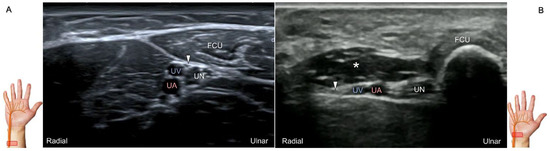

Scanning Technique

To locate the Guyon’s canal, the transducer is placed along the axial plane on the volar wrist with the forearm supinated. This will reveal the ulnar nerve and artery within the canal (Figure 13A). To investigate the nerve’s long axis, the transducer is rotated 90 degrees. By moving the transducer toward the finger, the superficial and deep branches can be seen. Between the pisiform and hamate, the superficial and deep branches (along with their accompanying vessels) can be visualized as separated by the fibrous arch of hypothenar muscles, respectively (Figure 13B) [39].

The superficial branch divides into two palmar digital nerves. They run superficially along the little finger and half of the ring finger. The deep branch, on the other hand, can be observed between the flexor digiti minimi brevis and opponens digiti minimi muscles before it penetrates the deep aspect of the palm (Figure 13C). By pivoting the transducer, the physician can display the long axis of the deep branch, extending all the way to the segment within the adductor pollicis muscle (Figure 13D).

Figure 13. Sonographic imaging (short-axis view) shows the ulnar nerve within the Guyon’s canal (A), separation of branches beside the pisohamate hiatus (B), deep branch of the ulnar nerve located between the hypothenar muscles distal to the hook of the hamate (C). Long-axis view (through pivoting the transducer) shows the segment of the deep branch within the adductor pollicis muscle (D). Arrowhead: ulnar nerve; white arrows: superficial branch of the ulnar nerve; black arrows: deep branch of the ulnar nerve; orange arrow: branch of the ulnar nerve to the abductor digiti minimi; *: pisohamate ligment MN: median nerve; UA: ulnar artery; P: pisiform; H: hook of hamate; A: artery; L: lumbrical muscle; FDM: flexor digiti minimi brevis muscle; Opp DM: opponens digiti minimi muscle; AbDM: abductor digiti minimi muscle; AdP: adductor pollicis muscle.